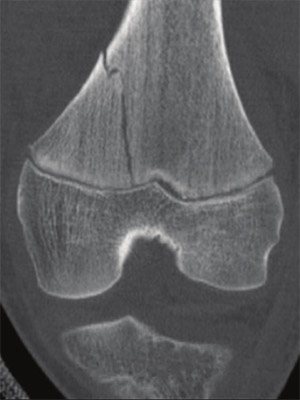

In the distal femur module, the management of all relevant metaphyseal and epiphyseal fracture types is covered with procedures for immobilization and fixation with K-wires, screws, and/or plates.